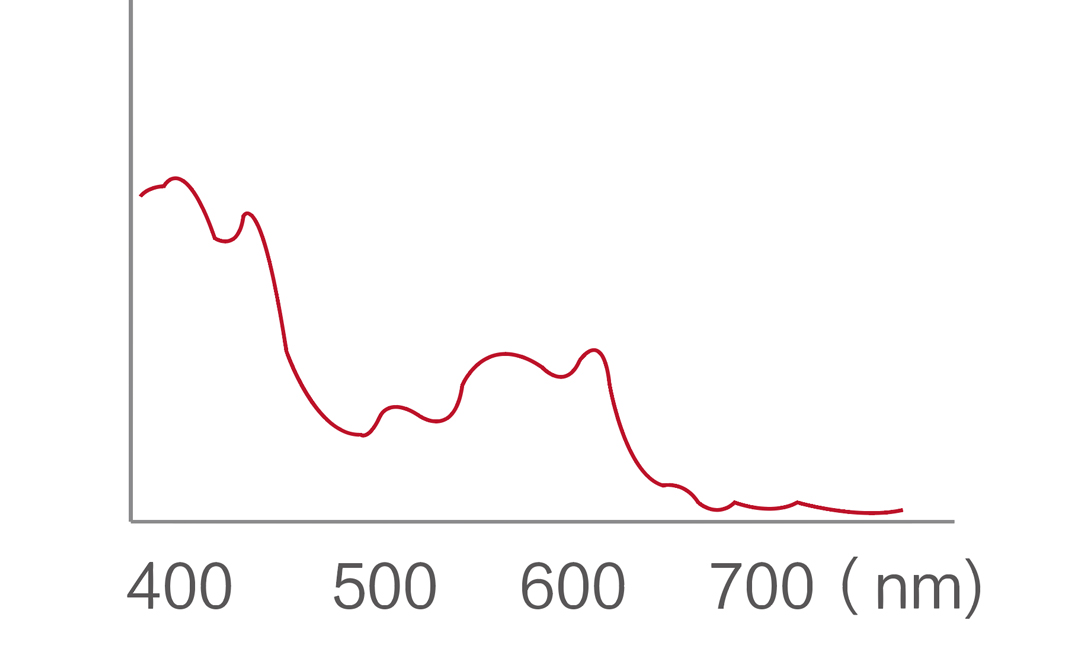

百老汇电子游戏官网新开发的内镜染色技术,主要是基于多波长LED 光源的开发,VLS-55Q 四波长LED 光源是由四个不同颜色的LED光按照相应照明模式所规定的特定发光比例进行合束后形成,合束后形成的照明光的光谱由红光、绿光、蓝光及蓝紫光这四个不同的波段范围构成。具有更高光谱自由度,通过光谱比例的控制,实现了聚谱成像技术,英文全称为“Spectral Focused Imaging, SFI”,缩写为“SFI”和光电复合染色成像技术,英文全称为“Versatile Intelligent Staining Technology, VIST”,缩写为“VIST”。